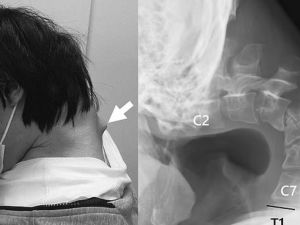

Japanese man gets 'dropped head syndrome' after using his phone too much